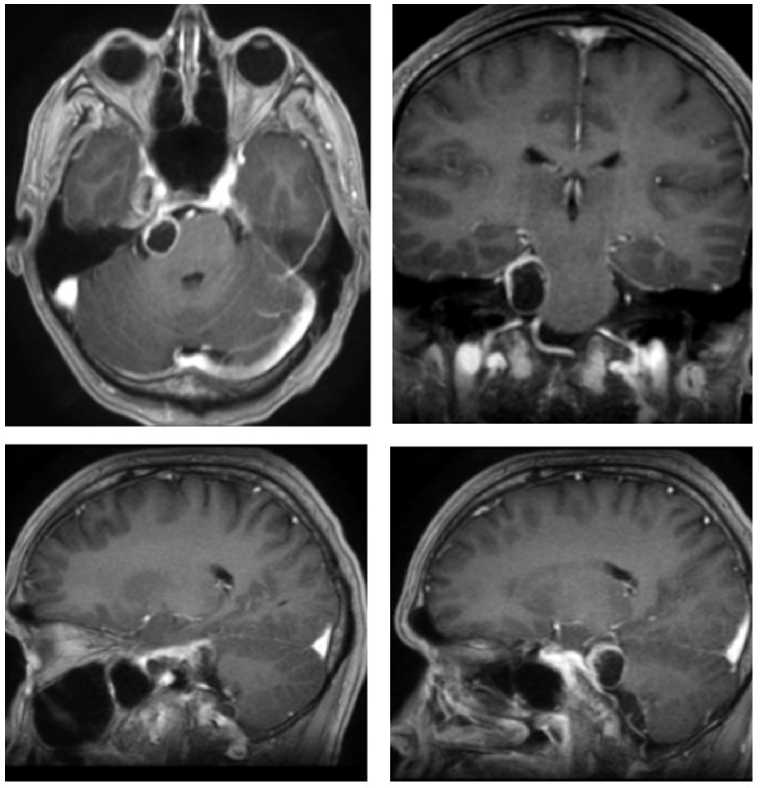

Через 6 мес. после операции пациенту проведено лучевое лечение на аппарате Кибер-нож в режиме радиохирургии. Разовая доза — 13,52 Гр, объем облученной опухоли составил 3,46 см3. На МРТ перед лучевой терапии визуализирован фрагмент невриномы тройничного узла в СЧЯ справа размерами 1,56 × 1,59 × 1,35 см, объем опухоли 2,46 см3 (рис. 6). В клинической картине на момент облучения сохранялась гипестезия и снижение роговичного рефлекса, однако через 3 мес. присоединились парестезии в лице и слабость жевательной и височной мышц на стороне операции.

Через 1 г. после лучевой терапии в клинической картине пациент отмечает частичное восстановление чувствительности на лице, а также появление недостаточности VIII черепного нерва справа. Контрольная МРТ продемонстрировала уменьшение опухоли, размеры — 1 × 1,88 × 0,74 см, объем — 0,73 см3 (рис. 6).

Рис. 6. МРТ пациента О.: А — перед лучевой терапией: невринома в СЧЯ, опухоль в ЗЧЯ удалена тотально; Б — через 6 мес. после лучевой терапии: небольшой остаток опухоли в СЧЯ; В — через 1 г. после лучевой терапии: небольшой остаток опухоли в СЧЯ

Fig. 6. MRI of patient O.: A — before radiation therapy: neuroma in MCF, tumor in PCF completely removed; Б — 6 months after radiation therapy: small tumor remnant in MCF; В — 1 year after radiation therapy: small tumor remnant in MCF